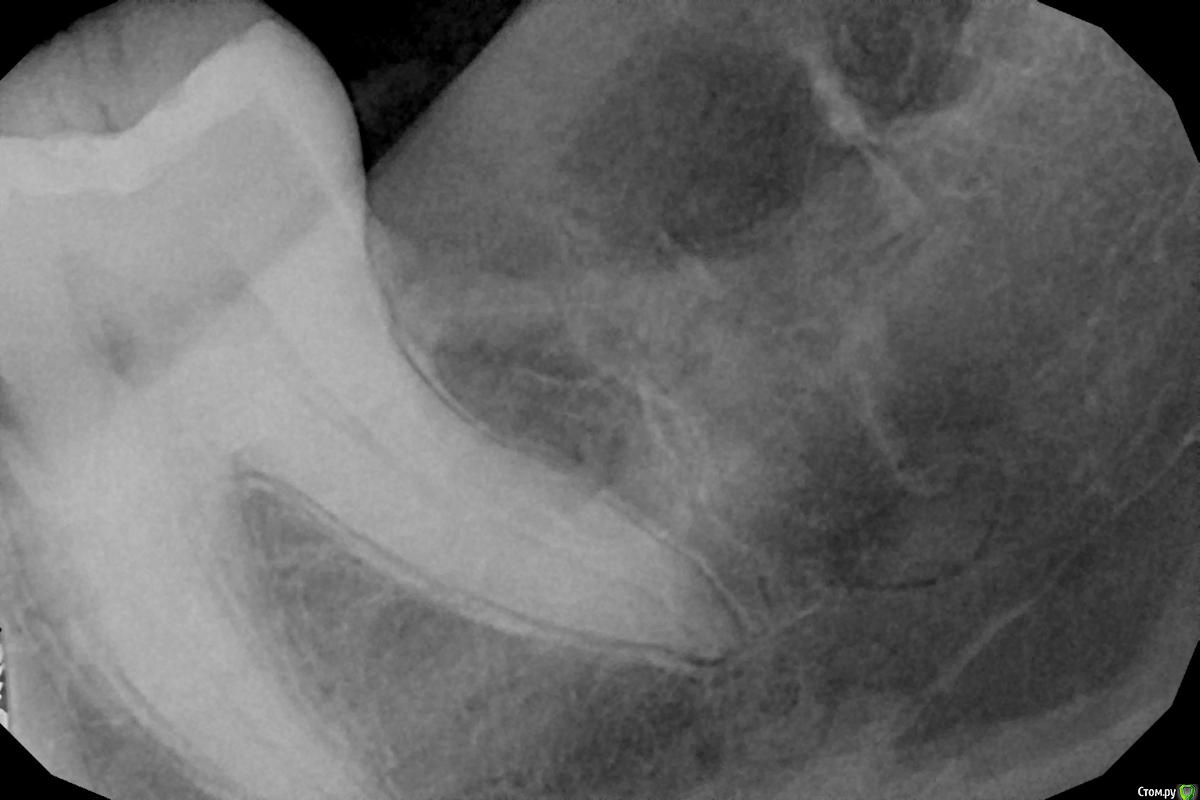

Аслан Опубликовано 2 февраля, 2015 Поделиться Опубликовано 2 февраля, 2015 Вот такой 28 у коллеги убрал пару часов назад. http://s018.radikal.ru/i509/1502/33/458d2fae3a7ft.jpg 6 Ссылка на комментарий

red_butler Опубликовано 3 февраля, 2015 Поделиться Опубликовано 3 февраля, 2015 Вот такой 28 у коллеги убрал пару часов назад. зуб оказался самцом 3 Ссылка на комментарий

Shargik Опубликовано 17 февраля, 2015 Поделиться Опубликовано 17 февраля, 2015 Удаляйте фото из цитат28? красивый) 1 Ссылка на комментарий

SDC Опубликовано 17 февраля, 2015 Поделиться Опубликовано 17 февраля, 2015 28? красивый)+ Ссылка на комментарий

Orient Опубликовано 17 февраля, 2015 Поделиться Опубликовано 17 февраля, 2015 28? красивый)Усейн Болт 2 Ссылка на комментарий